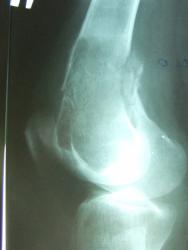

Патологический перелом дистального метафиза бедра, в котором определяется большой участок деструкции многокамерной структуры, занимающий весь поперечник кости, окаймленный ободком склероза, слегка вздувающий кость. Кортикальный слой резко истончен. Остеопороз в проксимальном эпиметафизе б/берцовой кости. Склоняюсь к костной кисте. Через 2 года на месте перелома динамика развития склеротических изменений (тенденция к самоизлечению кисты? хотя не могу исключить замещение ткани кисты трансплантатом, т.е. оперативное вмешат-во), уменьшение выраженности остеопороза в проксим. эпиметафизе б/берцовой кости.

Представлен случай гиперпаратиреоидной остеодистрофии. А лечение соответственно - удаление аденомы паращитовидной железы. На кости операций не было.